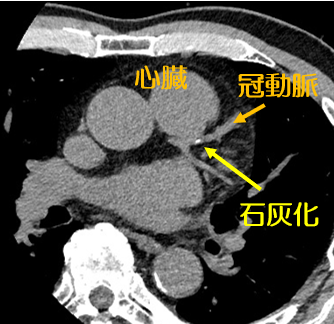

冠動脈は心臓を栄養する大切な血管です。しかし動脈硬化が進行すると石灰化などが血管壁に沈着して狭窄を起こし、狭心症や心筋梗塞などの原因となります。

CT検査の画像から血管壁の石灰化の沈着度合いを数値で表したものを石灰化スコアといいます。

CT画像は後日結果説明をご希望いただければ診察室のモニターで閲覧とご説明が可能です。